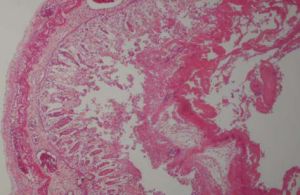

疾病病理

壞死性腸炎上有纖維素性偽膜本病起病急驟,1/3可有不潔飲食史。臨床以急性腹痛、腹脹、嘔吐、腹瀉、便血及全身中毒症狀為主要表現。